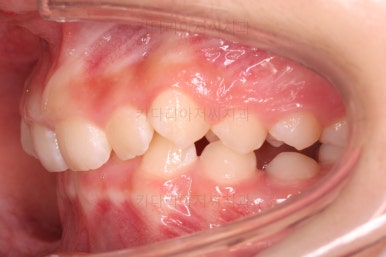

초진 시 입안의 모습입니다.

앞니가 안으로 굽어 들어간 양상인데요. 흔히 "옥니"라고 표현합니다.(뻐드렁니의 반대개념)

전반적으로 치열이 삐뚤삐뚤하고요.

오른쪽 상단 사진을 보시면 어금니의 높이와 앞니의 높이가 차이가 많이 납니다.

앞니가 솟구쳐 있는 양상인데요.

그 이유 때문에 어금니로 다물었을 때의 위아래 앞니가 많이 겹쳐서 아래 앞니가 아예 보이지 않는 상황이었어요.

이를 "과개교합"이라고 표현합니다.

그리고 전반적으로 아래 치열이 윗니에 비해 뒤로 밀려 있어서, 어금니의 맞물림이 좋지 못하고 듬성듬성해 보이는 상황이었어요.